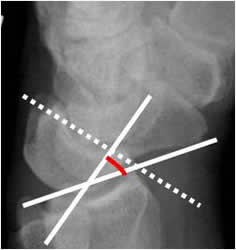

Angulo grandelunado:

Con una amplitud normal entre 0º y 30º. El eje del hueso grande se traza de la parte media de la cabeza, a la parte mas inferior de su superficie articular.

En la inestabilidad tipo DISI (dorsal inestabilidad del segmento intercalado), se aprecia desplazamiento anterior y angulación dorsal del lunado, con aumento de los ángulos escafolunado por desplazamiento anterior del escafoides y del grandelunado por desplazamiento dorsal del lunado (27, 28). (Fig 53 y 54).

Fig 53. Angulo grandelunado.

A: Rx lateral de muñeca. Intersección entre los ejes de los huesos grande y lunado.

Fig 54. Inestabilidad tipo DISI.

A: Rx lateral de muñeca. Angulo escafolunado mayor de 60.